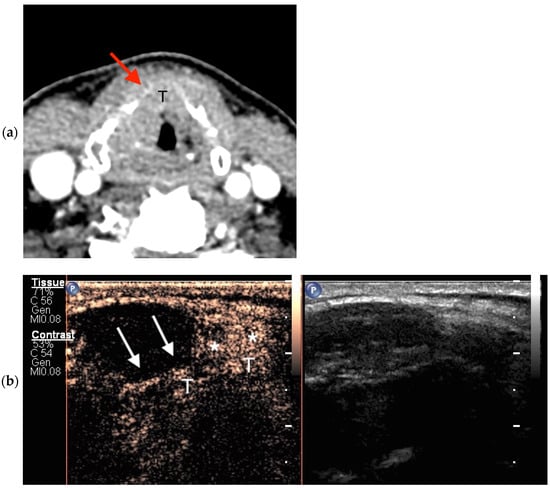

2.5.1. CEUS Imaging

2.5.2. Cross-Sectional Imaging